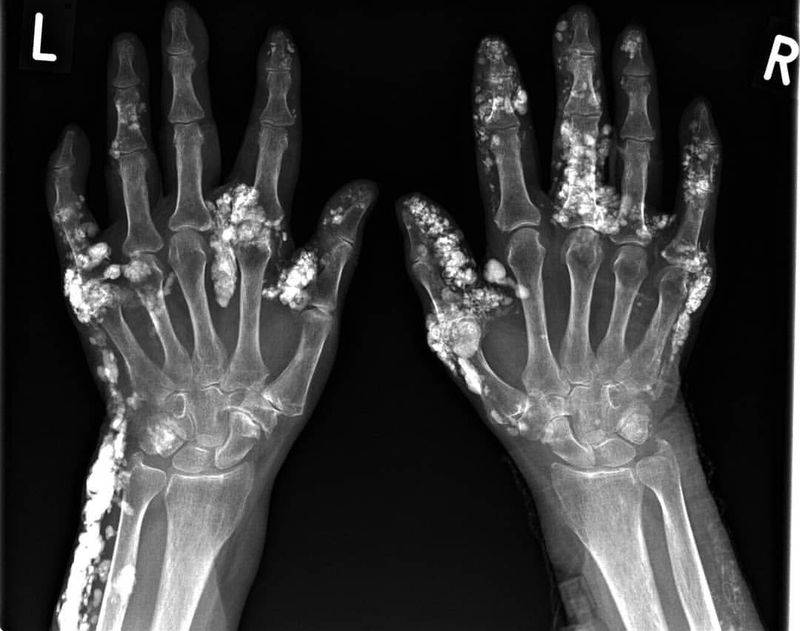

Scleroderma is a group of autoimmune diseases that may result in changes to the skin, blood vessels, muscles, and internal organs. The disease can be either localized to the skin or involve other organs in addition to the skin. Symptoms may include areas of thickened skin, stiffness, feeling tired, and poor blood flow to the fingers or toes with cold exposure. One form of the condition, known as CREST syndrome, classically results in calcium deposits, Raynaud's syndrome, esophageal problems, thickening of the skin of the fingers and toes, and areas of small dilated blood vessels The cause is unknown; however, some suspect it may be due to an abnormal immune response.Risk factors include family history, certain genetic factors, and exposure to silica. Typical scleroderma is classically defined as symmetrical skin thickening, with about 70% of cases also presenting with Raynaud's phenomenon, nail-fold capillary changes and antinuclear antibodies. Affected individuals may or may not experience systemic organ involvement. There is no single test for scleroderma that works all of the time and hence the diagnosis is often a matter of exclusion. Atypical scleroderma may show any variation of these changes without skin changes or with finger swelling only. Laboratory testing can show antitopoisomerase antibodies, like anti-scl70 (causing a diffuse systemic form), or anticentromere antibodies (causing a limited systemic form and the CREST syndrome). Other autoantibodies can be seen, such as anti-U3 or anti-RNA polymerase.[25] |- Anti-double-stranded DNA (ds DNA) autoantibodies likely to be present in serum.